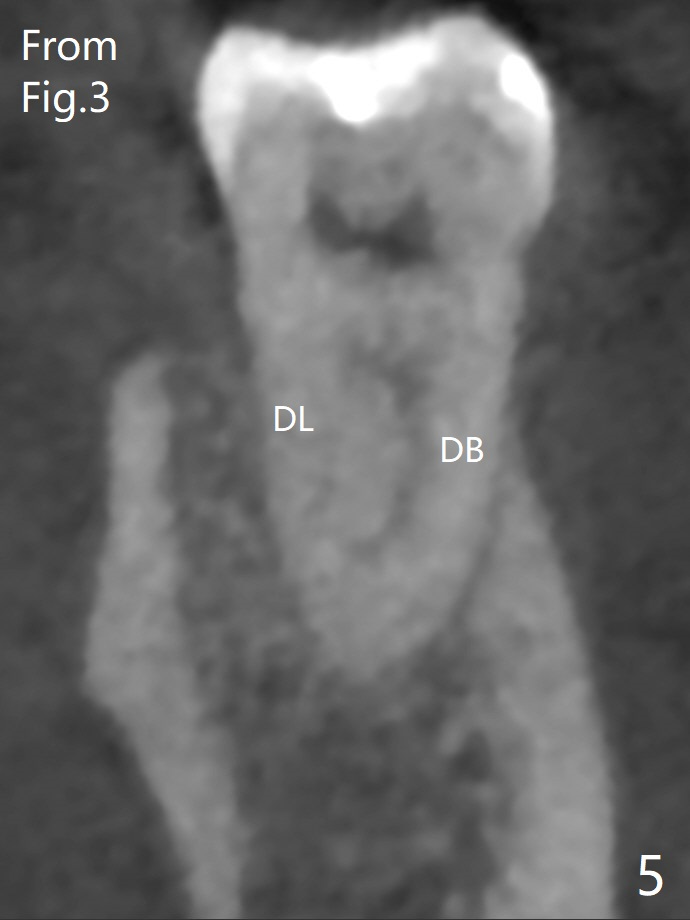

A 61-year-old man may have referral pain between #17 and 18. The canals at #18 are narrower than those at #17 (Fig.1-3). If #18 needs RCT, blocks should be removed (Fig.4-6 vs. 4'-6').